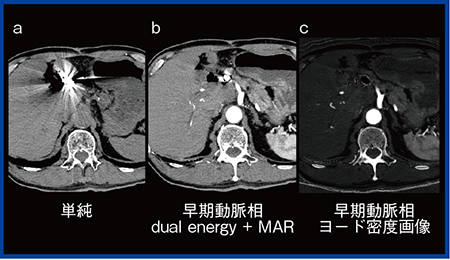

肝動脈塞栓術(transcatheter arterial embolization:TAE)後は,金属などの塞栓物質を使用するため,通常CT ではアーチファクトを生じてしまい血管評価は難しい(図2 a)。そこでdual energy CT(70keV)と金属アーチファクト低減処理MAR(metal artifact reduction)を併用することで,コイル周囲のアーチファクトが軽減され,血管視認性が向上する(図2 b)。さらに,物質密度画像(ヨード密度画像)を用いることによって,コイルが消失し周囲の血管評価が可能になる(図2 c)。物質密度画像はCT値ではなく物質密度値になるため,サードパーティ製ワークステーションで処理できないこともあるが,REVORASでは物質密度画像による3D作成が可能である(図3 a)。ただし,物質密度画像は密度値のレンジが狭く3Dが作成しにくい場合がある。そこで,笹森らが頭部領域で考案した手法を応用した,40keVと140keVによるエネルギーサブトラクションを用いて作成したのが図3 bである2)。本手法を用いると,腹部領域でも血管視認性の高い3D画像が作成できている。

図2 TAE後血管評価